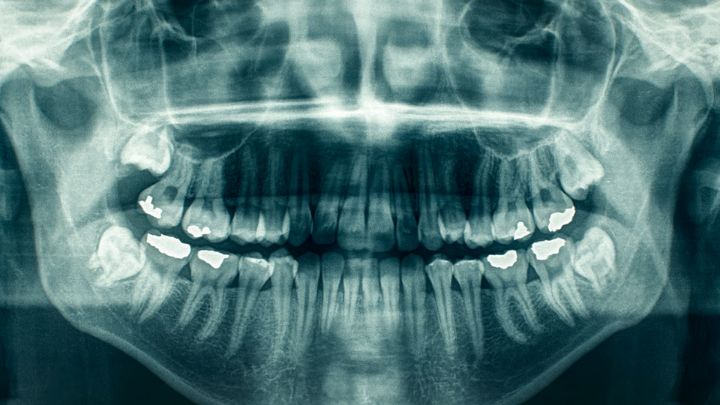

A inteligência artificial (IA) está sendo cada vez mais integrada na teleodontologia para auxiliar no diagnóstico remoto. Algoritmos de IA podem analisar imagens enviadas pelos pacientes, identificando problemas como cáries, doenças gengivais e outros distúrbios bucais. Isso permite diagnósticos mais rápidos e precisos.